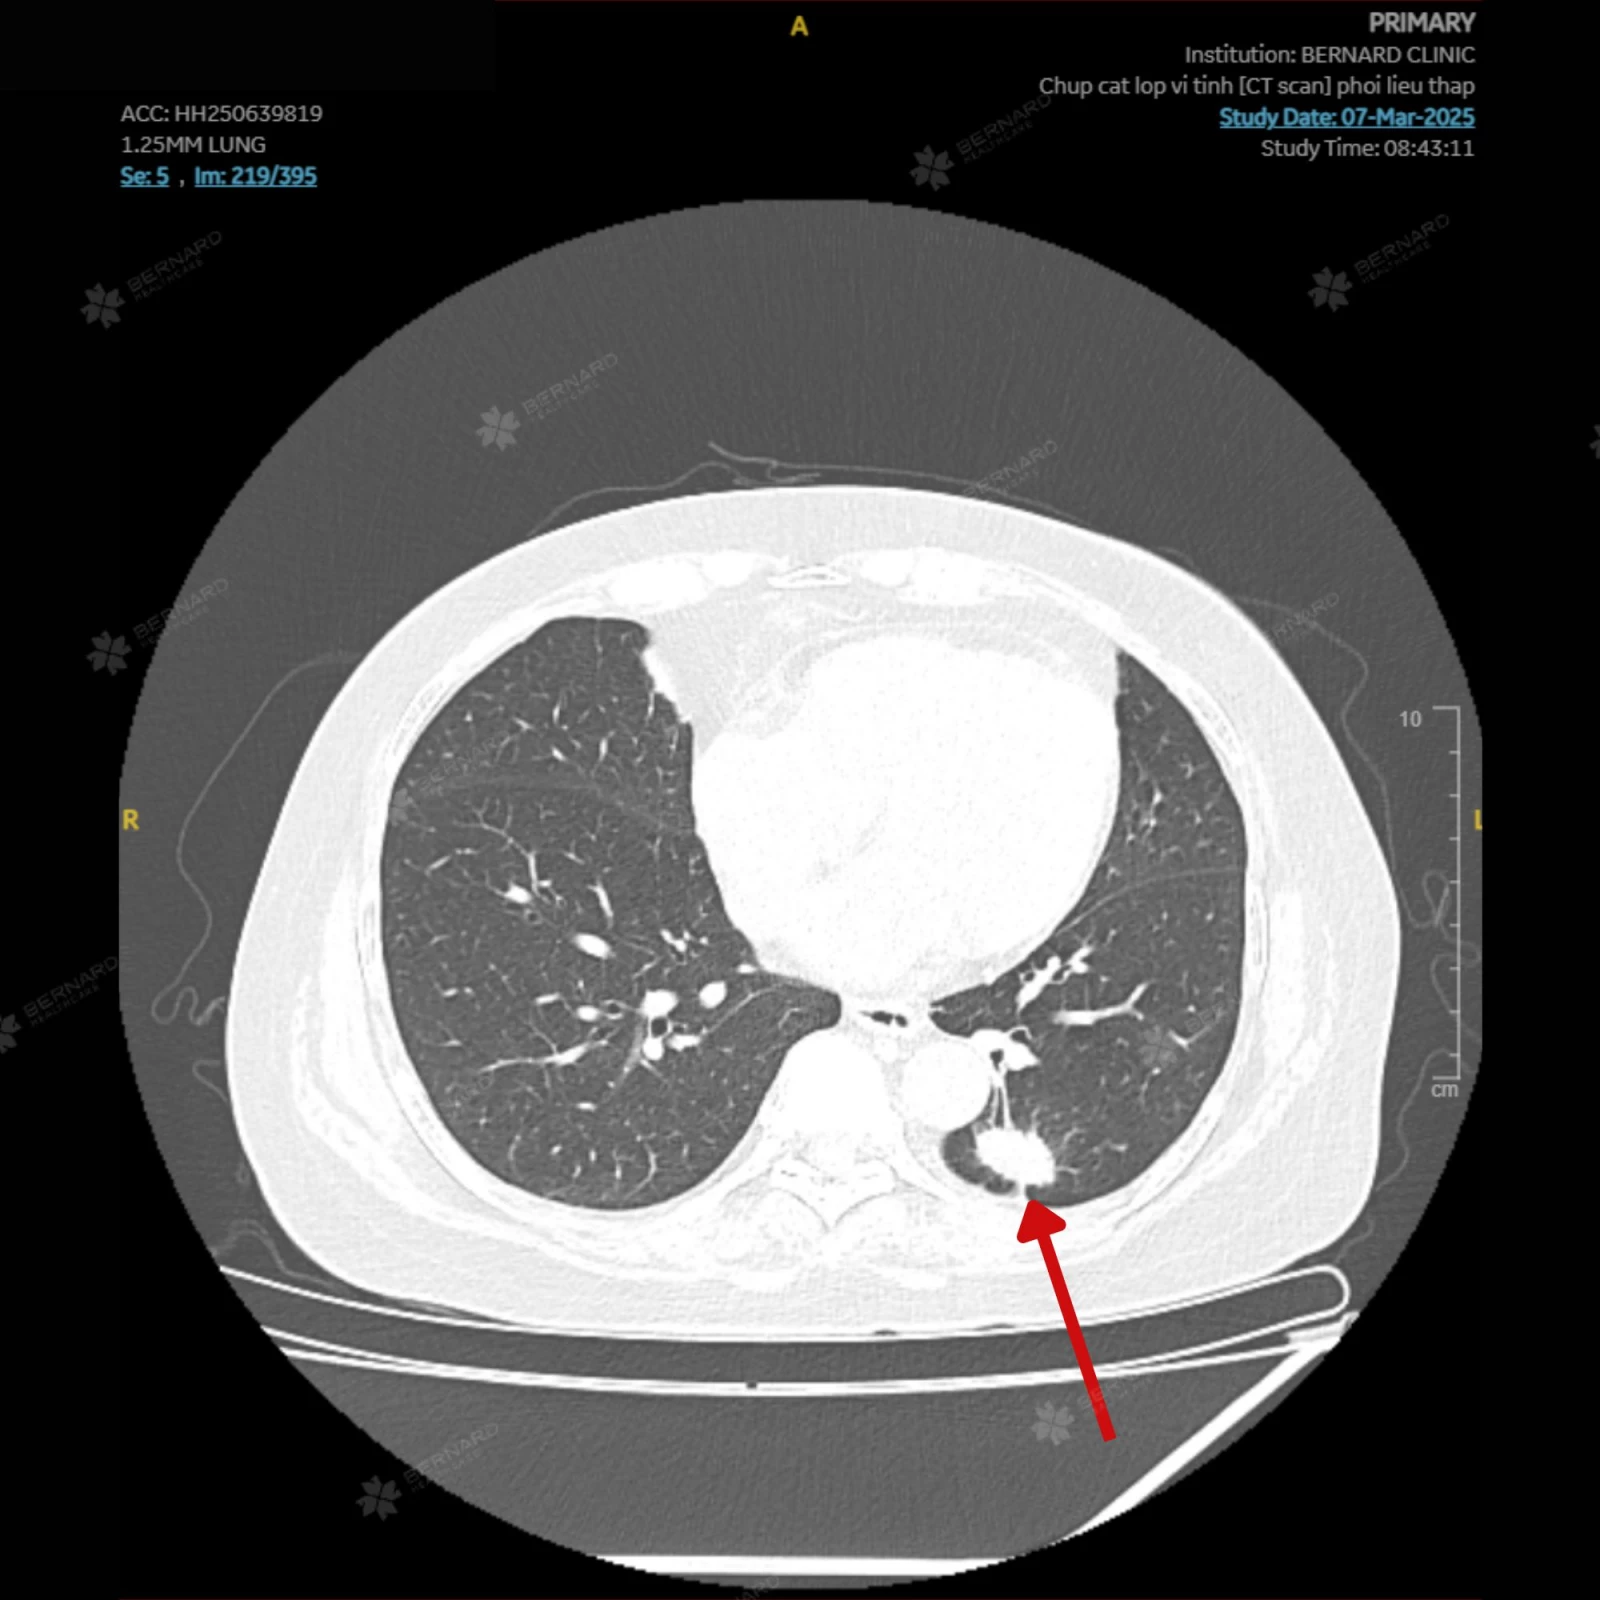

Kết quả CT Scan phổi liều thấp cho thấy một tổn thương choán chỗ thùy dưới phổi trái (S10), kích thước khoảng 1.5 x 2.5cm, đậm độ mô, bờ tua gai, kèm co kéo mô phổi xung quanh. Những đặc điểm hình ảnh này gợi ý u phổi ác tính - cần kết hợp sinh thiết để xác định chính xác bản chất của tổn thương.

Đáng chú ý, kết quả CT Scan phổi còn đồng thời ghi nhận một số hạch trung thất nghi di căn với hạch lớn nhất thuộc nhóm 2, các nốt nhỏ quanh rãnh liên thùy bé phổi phải (đường kính khoảng 3mm) và nốt dưới màng phổi thùy lưỡi (đường kính khoảng 7mm). Đây có thể là dấu hiệu tổn thương đã bước vào giai đoạn di căn hạch trung thất. Tuy nhiên, chưa ghi nhận bằng chứng lan rộng ra các cơ quan xa.